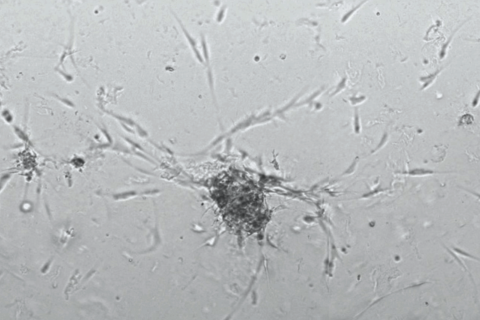

Second, and in parallel, the lab focuses on developing clinically-relevant organoid models for cancer biology, as well as drug discovery and development applications. In particular, they establish tumor organoids from surgical specimens (patient-derived tumor organoids) and perform high-throughput drug screenings to individualize cancer therapy to each patient.